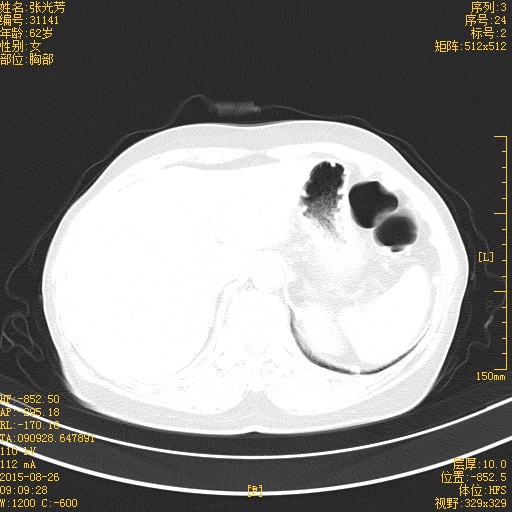

CT51093:双肺弥漫性病变考虑什么疾病

本帖最后由 cefcmj 于 2015-9-1 12:47 编辑 干咳一年多,无咯血病史。

右肺癌广泛转移

多发肺转移

肺癌肺转移